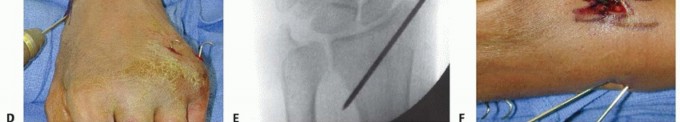

TECH FIG 3 •(continued)D. A pin is inserted retrograde into the radial styloid. E. PA radiograph demonstrating the course of the radial styloid wire. F. Two radial styloid wires and two dorsoulnar wires are in place. G. PA view showing fixation and the path of the wires. H. Lateral view showing fixation and path of wires. I. Pins are bent, cut, and covered above the skin. The pins are cut just beneath the skin, which is closed with a 5-0 nylon suture. Alternatively, the pins are bent and cut and left outside the skin ( TECH FIG 3I). A dressing and splint are then applied.3. Bridging External Fixator Application